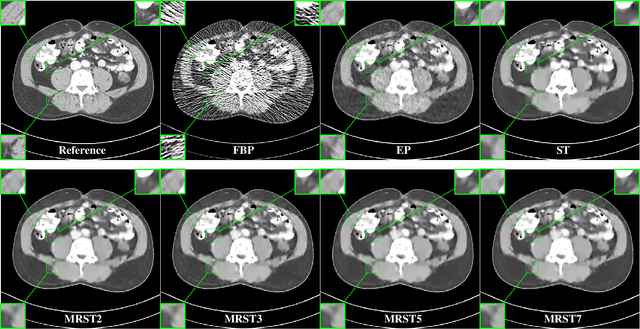

Abstract:Signal models based on sparse representation have received considerable attention in recent years. Compared to synthesis dictionary learning, sparsifying transform learning involves highly efficient sparse coding and operator update steps. In this work, we propose a Multi-layer Residual Sparsifying Transform (MRST) learning model wherein the transform domain residuals are jointly sparsified over layers. In particular, the transforms for the deeper layers exploit the more intricate properties of the residual maps. We investigate the application of the learned MRST model for low-dose CT reconstruction using Penalized Weighted Least Squares (PWLS) optimization. Experimental results on Mayo Clinic data show that the MRST model outperforms conventional methods such as FBP and PWLS methods based on edge-preserving (EP) regularizer and single-layer transform (ST) model, especially for maintaining some subtle details.

Abstract:Signal models based on sparsity, low-rank and other properties have been exploited for image reconstruction from limited and corrupted data in medical imaging and other computational imaging applications. In particular, sparsifying transform models have shown promise in various applications, and offer numerous advantages such as efficiencies in sparse coding and learning. This work investigates pre-learning a multi-layer extension of the transform model for image reconstruction, wherein the transform domain or filtering residuals of the image are further sparsified over the layers. The residuals from multiple layers are jointly minimized during learning, and in the regularizer for reconstruction. The proposed block coordinate descent optimization algorithms involve highly efficient updates. Preliminary numerical experiments demonstrate the usefulness of a two-layer model over the previous related schemes for CT image reconstruction from low-dose measurements.